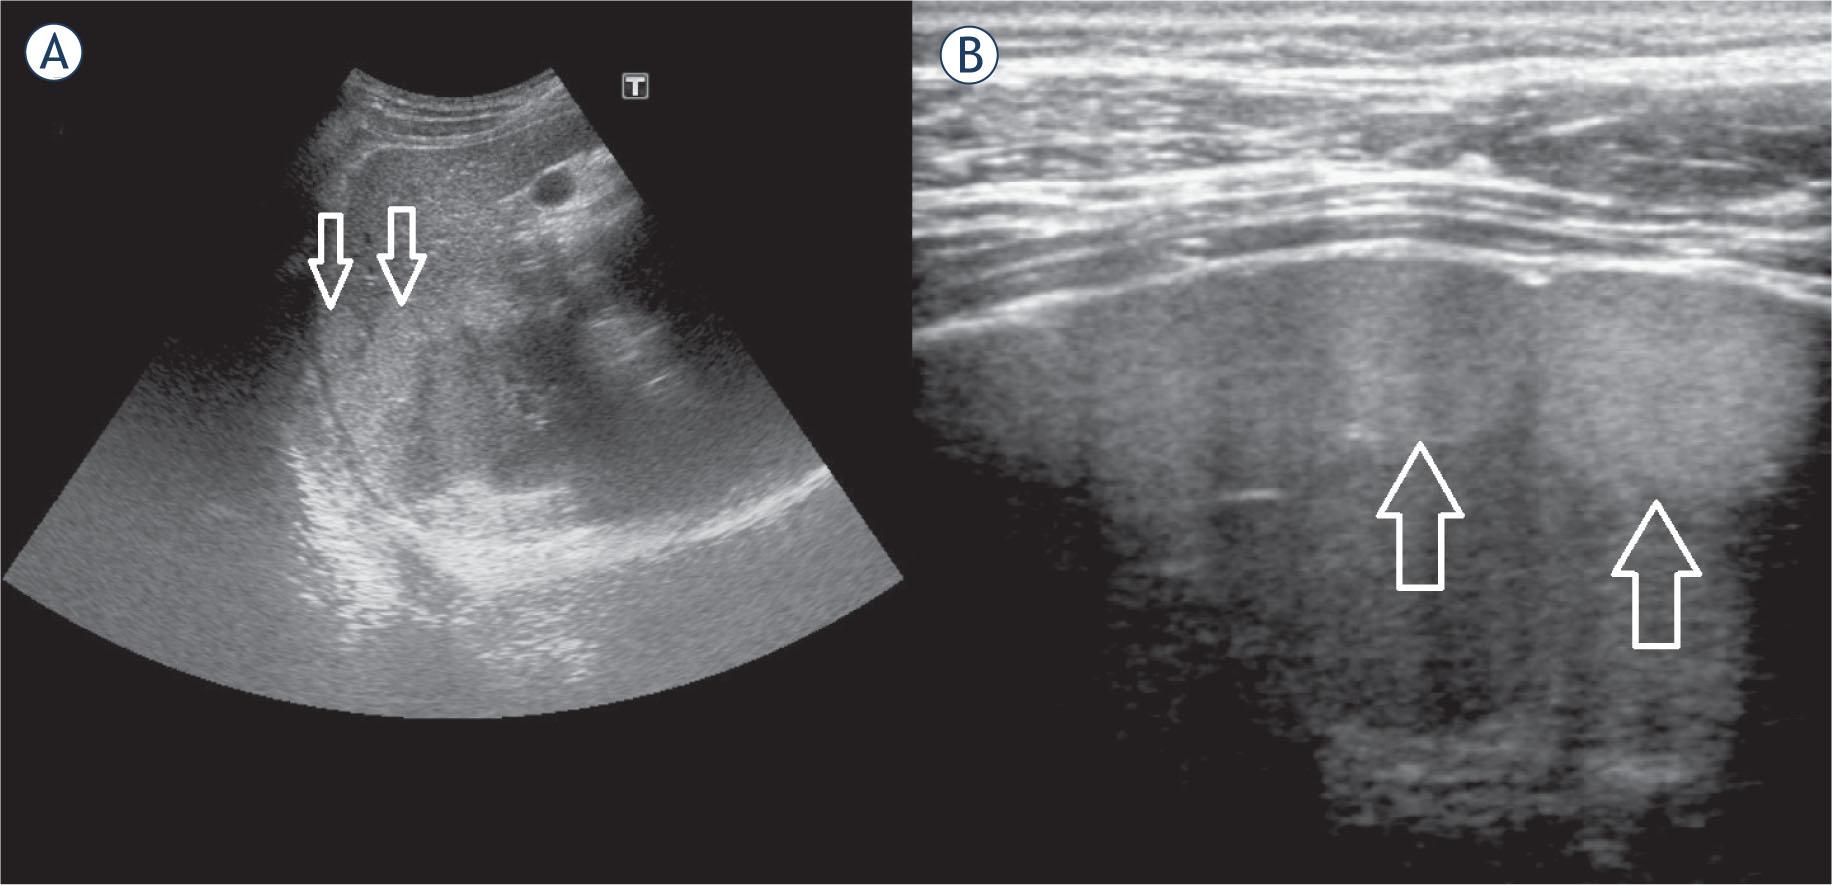

US; mildly hyperechoic subcapsular hepatic lesions; (A)abdominal probe; (B)high frequency linear probe.